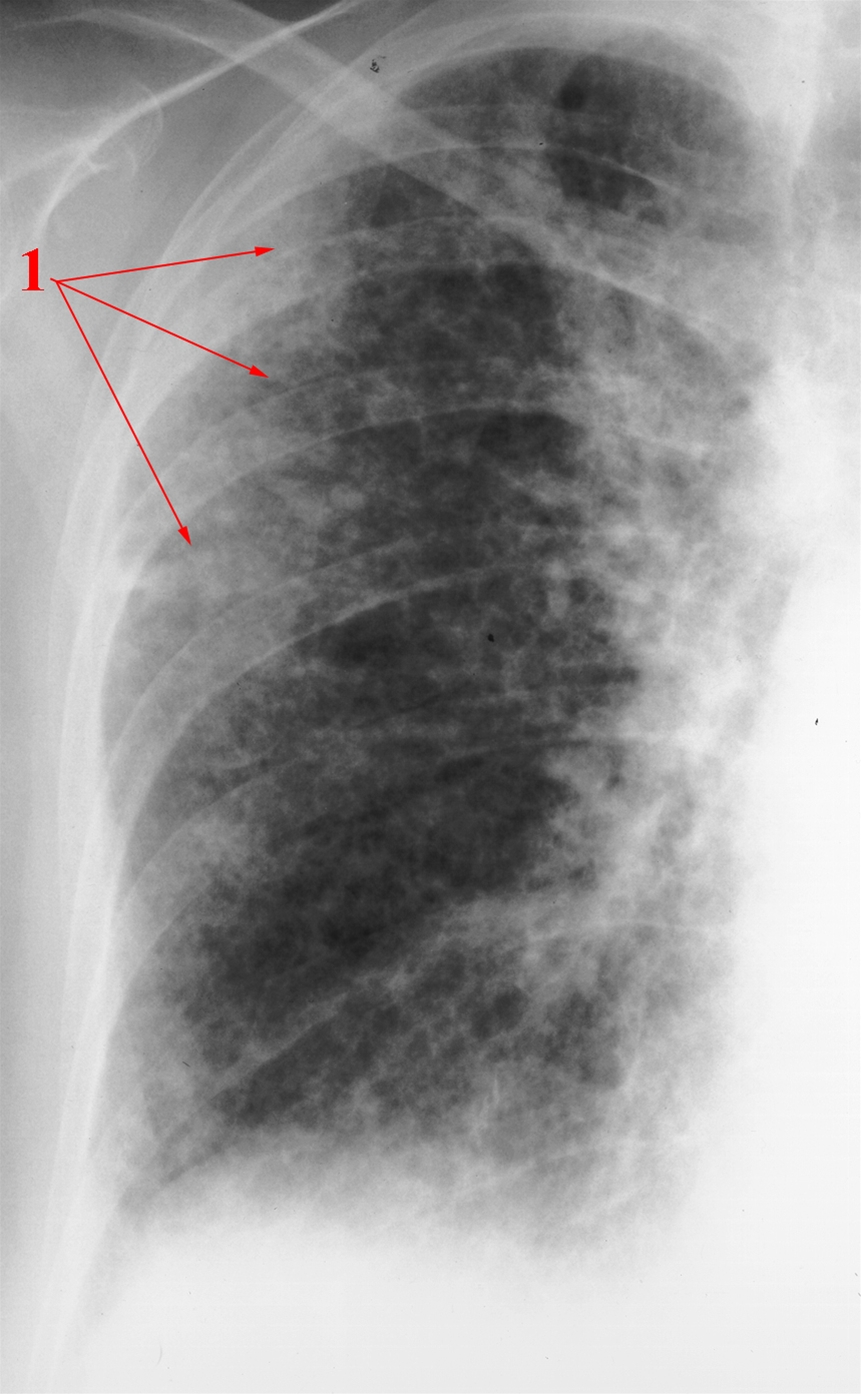

Lungefibrose, røntgen

Udbredte, overvejende stribeformede (reticulære) fortætninger i periferien af lungen (1).